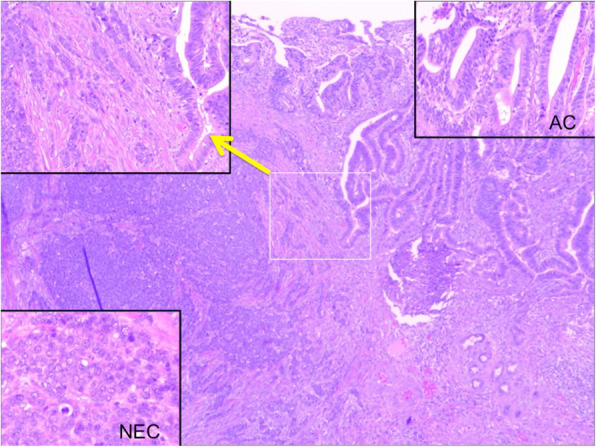

Under a diagnosis of primary cholangiocarcinoma (CCA) of the DBD, a subtotal stomach-preserving pancreaticoduodenectomy was performed. Neither peritoneal dissemination nor lymph node metastases were found during the operation. Macroscopically, an irregularly shaped nodular tumor was found in the DBD (Fig. 4). Microscopically, the lesion was seen to be composed of predominantly well-differentiated tubular AC in the superficial layer of the tumor, admixed with neuroendocrine carcinoma (NEC) in the deeper portion (Fig. 5), indicating a diagnosis of MANEC of the DBD. While the AC component shows papillary growth toward the lumen of the bile duct, the NEC component had infiltrated into the muscle layer, with vascular and neural invasion. Atypical epithelium was found extensively in the superficial epithelium and accessory glands of the CBD, but no malignancies were found in the gallbladder, cholecystic duct, papilla of Vater, pancreas, or duodenum; based on this, the final pathological diagnosis was MANEC of the CBD, Pat Bi, fm, pPanc0, pDu0, pHM0, pEM0, tubular, well-differentiated tubular AC>NEC, INF β, int, ly0, v0, pm1. No lymph node metastases were found. After immunohistochemical staining, NEC components were diffusely positive for synaptophysin and CD56, and the MIB-1 index was 30% (Fig. 6). In both components, p16 was positive and p53 was negative. Additionally, the NEC component was strongly positive for SSTR2, SSTR5, and mammalian target of rapamycin (mTOR) (Fig. 7).

Making an accurate preoperative diagnosis of biliary NEN is extremely difficult due to its indefinite clinical and imaging characteristics; as a result, most MANECs of the bile duct are initially thought to be ACs or NETs [ref. 6, ref. 7, ref. 26]. A previous study examined 274 cases of surgically resected biliary tract cancer specimens and reported that 13 of 53 extrahepatic bile duct cancer cases contained neuroendocrine cells and 2 were newly diagnosed as MANEC [ref. 21]. Our patient was also first diagnosed with CCA by brush cytology, probably because the AC component was localized in the superficial layer and the NEC component was located in the deeper portion.